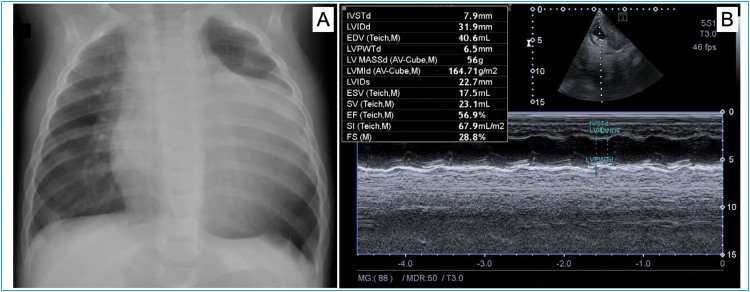

Case description: A 5-month-old male infant was admitted to the pediatric emergency department with acute viral bronchiolitis requiring hospitalization. He presented a detectable respiratory syncytial virus in oropharyngeal swab, blood test with lymphocytosis and a chest radiography revealed cardiomegaly. Further cardiologic testing was performed detecting elevation of cardiac biomarkers, an electrocardiogram with alteration of left ventricular repolarization and echocardiogram with a heterogeneous mass in the left ventricular, with areas of calcification. A chest angiotomography suggested rhabdomyosarcoma or cardiac fibroma and a magnetic resonance showed a mass, with characteristics suggesting fibroma. The final diagnosis was made after two cardiac catheterizations for biopsy of the lesion, confirming cardiac fibroma by anatomopathological examination. Because the patient had moderate to severe systolic dysfunction, he was submitted to heart transplant.